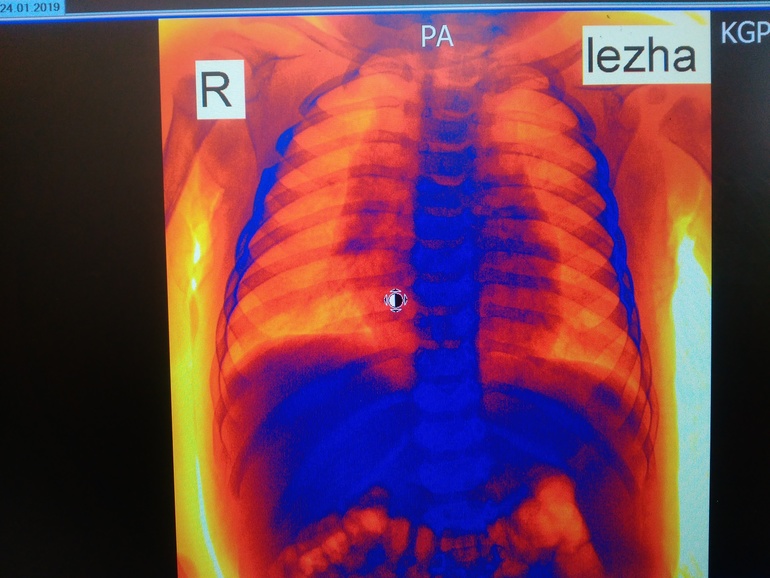

Всем здравствуйте! Сегодня ходили на рентген с сыночком на 6 месяцев,нас отправил хирург - выпирали нижние ребрышки. В итоге: сращение 4-5 ребра справа(никто такого поворота событий не ожидал,обнаружилось случайно),хондроматоз 6-7 ребра слева,кардиопатия. Завтра иду брать направление к хирургу-ортопеду в областной центр,но там скорее всего очередь. Хотела спросить девочки может кто-то с таким сталкивался? Может ошибка? Прикрепляются снимки (рентгенолог сам сказал сфотографируй потом покажешь врачу).Успокойте меня плииииззззз..